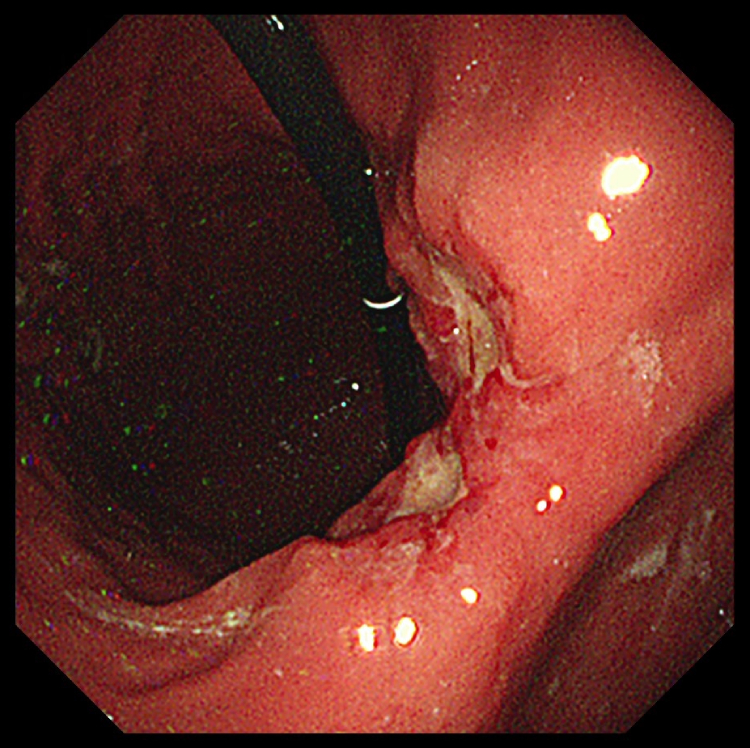

胃内視鏡検査(胃カメラ)

内視鏡で胃の内部を直接観察し、疑わしい病変があれば組織を採取(生検)し、病理診断を行います。

早期発見に最も有効な検査です。